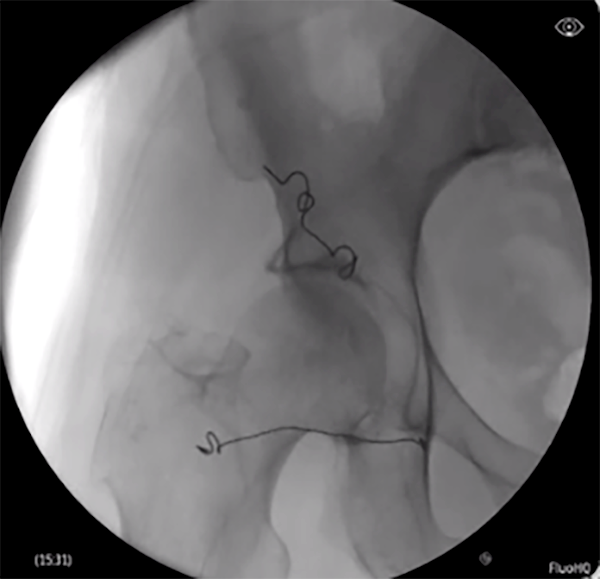

Neuromodulation devices targeting the dorsal root ganglion and nerves as well as nerve rootlets connecting into the DRG have technically challenging and time-consuming placement procedures. The Injectrode’s innovative placement procedure, with only 5 steps, has simplified how leads near the DRG can be placed. Relying on a transforaminal approach, similar to steroid injection pathways, present a development of a promising, minimally invasive alternative to the current standard of care.

The ‘scotty-dog’ landmark allows for repeatable injection of the device stimulator on the dorsal aspect of the roots as they exit the foramen. The delivery needle may be positioned between the likely location of the DRG and the pedicle at an oblique angle, then advanced off the bone to enter the dorsal aspect of the foramen. In this placement approach, the epidural space is not entered, and the Injectrode’s position relative to the ganglion enables stimulation.

Large animal and cadaver studies are underway to further characterize this placement approach.